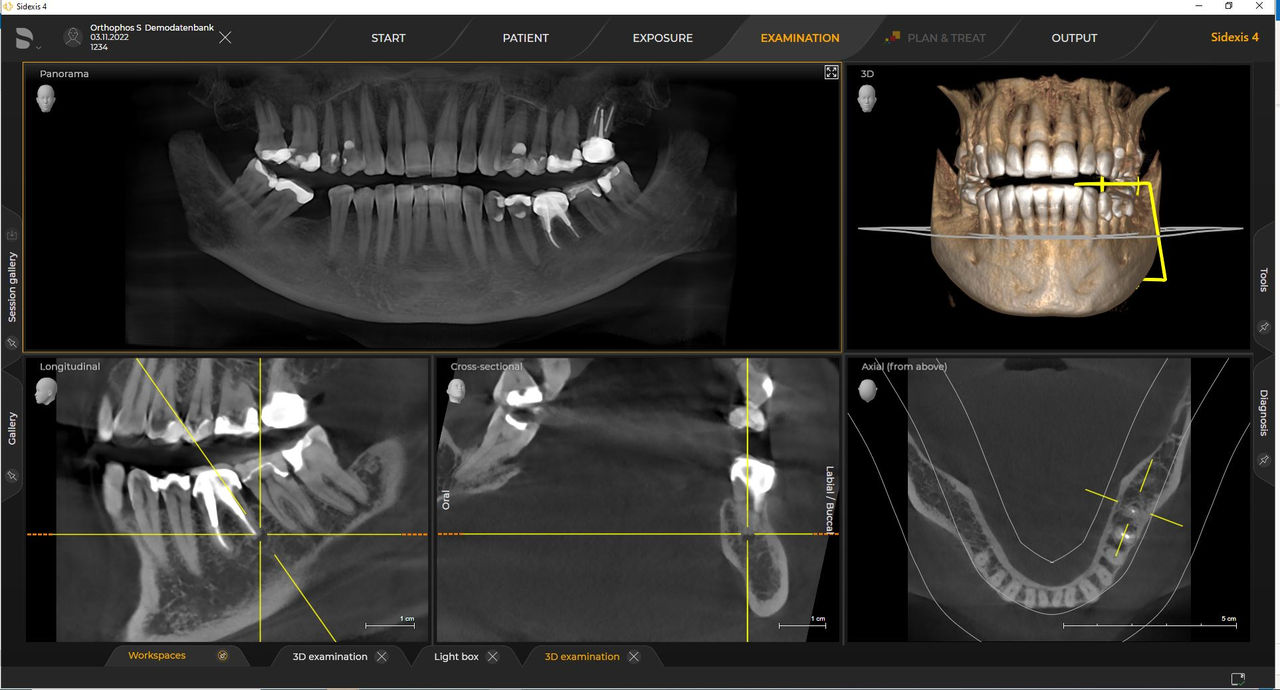

Las unidades de radiología de Dentsply Sirona funcionan exclusivamente con Sidexis 4. Sin embargo, la migración de datos de Sidexis XG a Sidexis 4 es muy fácil. Sidexis 4 permite una experiencia digital completa con las últimas herramientas

Los requisitos siguen los del software de procesamiento de imágenes Sidexis 4 y Orthophos S. Para obtener más detalles, consulte los requisitos del sistema Sidexis 4 y los requisitos de instalación de Orthophos S.